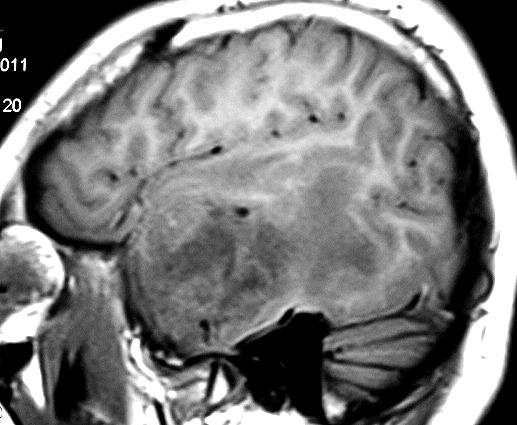

ГМ. Менингосаркома. +

Менингосаркома.